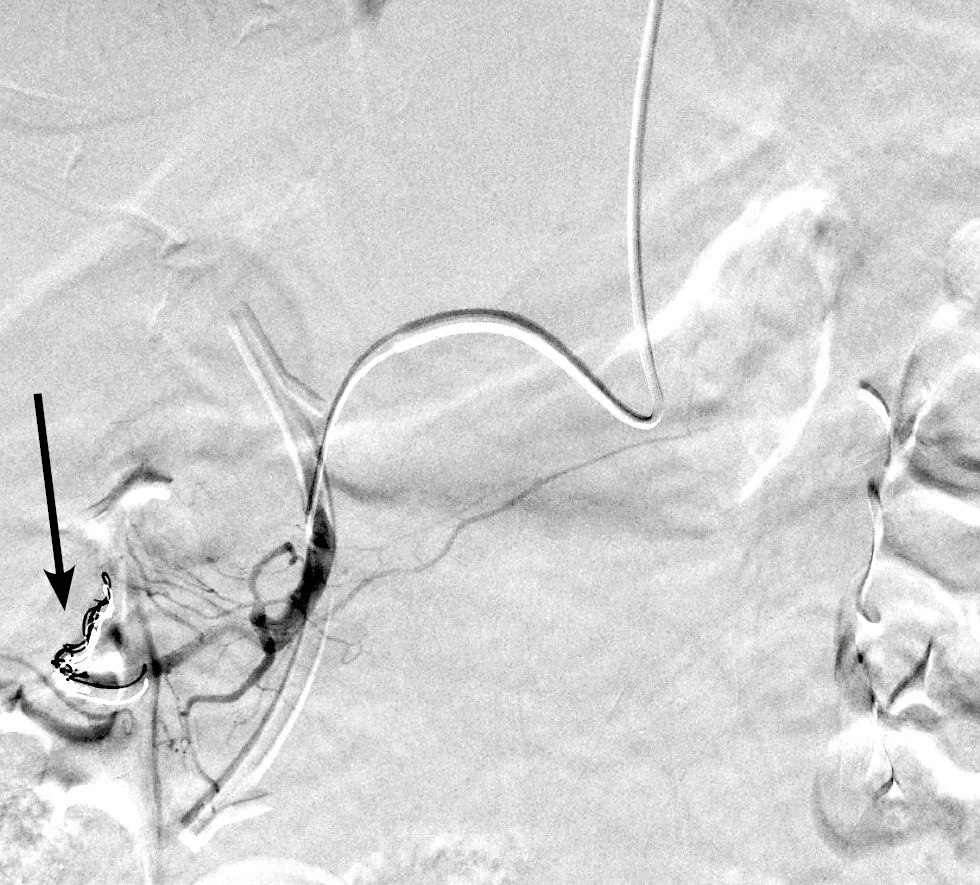

В обеих группах после выполнения ангиографии верхней брыжеечной артерии и чревного ствола (рис. 1) с помощью микрокатетера селективно катетеризировали правую желудочно-сальниковую артерию (рис. 2). С целью тотальной эмболизации опухоли поджелудочной железы и предотвращения нецелевой эмболизации применяли перераспределительную технику вмешательства: через упомянутый выше микрокатетер в правую желудочно-сальниковую артерию дистальнее отхождения всех кровоснабжающих опухоль ветвей последовательно имплантировали 2–3 толкаемые спирали (рис. 3), после чего вводили смесь липиодола в дозе 5 мл и гемцитабина в дозе 1000 мг (рис. 4).

Рис. 2. Ангиограмма правой желудочно-сальниковой артерии, выполненная через микрокатетер (чёрная стрелка).

Fig. 2. Angiogram of the right gastroepiploic artery, performed through a microcatheter (black arrow).